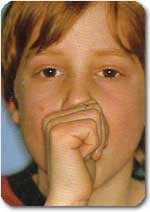

Habit Breaker یا عادت شکن جهت جلوگیری از مکیدن انگشت